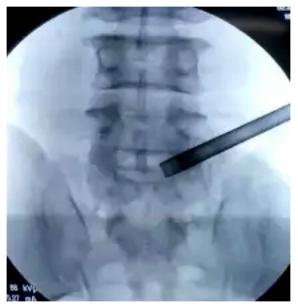

椎间孔镜手术

唐都医院脊柱神经外科王鹏教授

术中